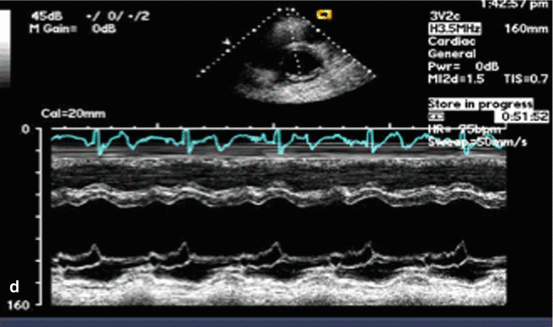

Austin Flint Murmur